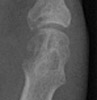

Gout Gout: Large erosion with overhanging edges 1st metatarsal

++